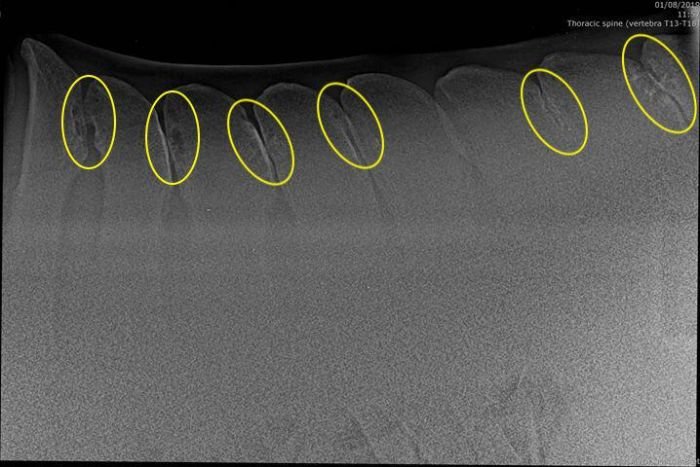

Toto je RTG snímek páteře koně, který trpěl bolestmi zad, nicméně i přesto byl jezditelný, jen vykazoval diskomfort pod sedlem. Žlutě jsou zvýrazněna místa, kde pozorujeme důsledek kontaktu trnových výběžků obratlů k sobě navzájem. Vidíte, že postižená oblast je poměrně rozsáhlá.